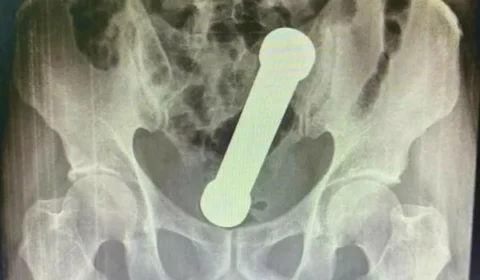

Homem é hospitalizado após procurar atendimento com peso de academia dentro do corpo, em Manaus

Homem de 54 anos procura hospital com dores abdominais e exame revela haltere de academia dentro do reto.

12/04/2022 19h35 Manaus